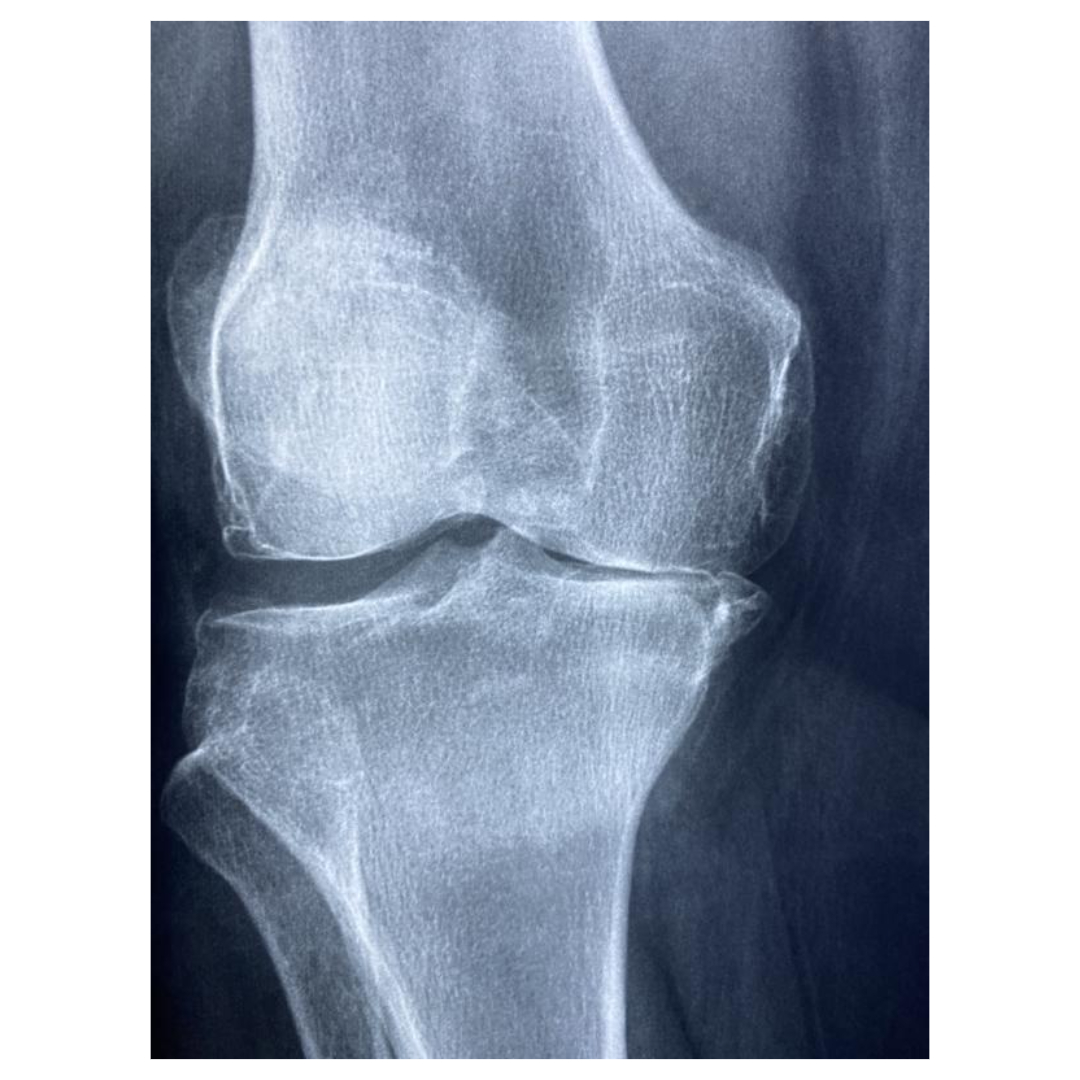

1. 심각한 관절 변형

손가락, 발가락뿐만 아니라 손목, 무릎 등의 관절에도 변형이 일어납니다. 관절이 휘어지거나 부러지듯 변형되며, 외관상으로도 뚜렷이 보이게 됩니다.

3. 기능 상실

관절이 완전히 손상되면 더 이상 움직일 수 없게 됩니다. 관절 내 연골이 닳아 없어지거나, 뼈가 직접 맞닿는 상황까지 이르기도 하며, 이로 인해 심한 통증과 함께 기능 상실이 발생합니다.